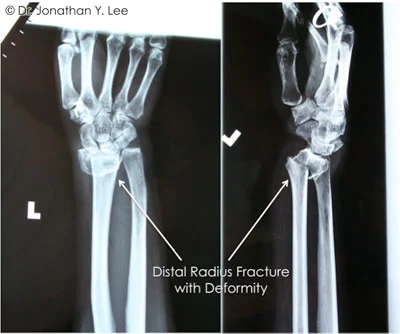

Figure 2 showing the distal radius fracture with deformity

The most commonly broken bone of the wrist is the radius (see Figure 1). When the wrist is broken, there is pain, swelling, and decreased use of the hand and wrist. The wrist often appears crooked and deformed (Figure 2).

Figure 3 showing distal radius fracture with deformity

Examination and x-rays (Figure 3) are needed so that your doctor can tell if there is a fracture and to help determine the treatment. Sometimes a CT scan or MRI may be used to get better detail of the fracture fragments and associated injuries. In addition to the bone, ligaments (the structures that hold the bones together), tendons, muscles, and nerves may also be injured when the wrist is broken and these injuries will need to be treated in addition to the fracture.